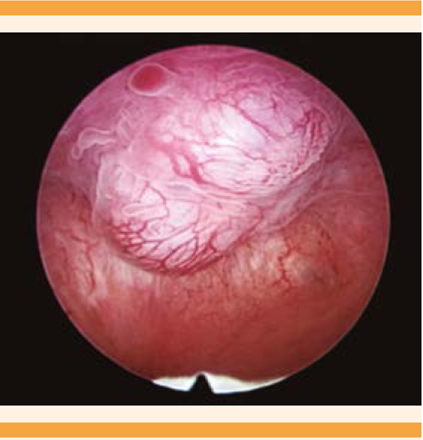

Un par de meses después se reinició la hemorragia uterina anormal, acompañada de dismenorrea incapacitante. El reporte de ultrasonido del mes siguiente reportó: útero en anteversoflexión de bordes regulares, miometrio heterogéneo, eco medio endometrial de 4 mm, en pared anterior y lateralizada a la izquierda una imagen anecoica, alargada, irregular, con grosor de 5 mm, que llegaba al fondo desde donde se proyectaba un trayecto vascular con flujo de alta velocidad hacia el borde distal de la cavidad endometrial (Figura 1). La histeroscopia diagnóstica reportó una lesión de tipo polipoide, pulsátil, irregular, sincrónica a frecuencia cardiaca, de 0.6 x 0.5 mm, localizada en la cara anterior izquierda (Figura 2). La biopsia endometrial se reportó con endometrio asincrónico, compatible con consumo de progestágenos. Se inició el tratamiento secuencial con análogo de GnRH (goserelina), implante subdérmico de 3.6 mg una dosis, más 500 mg cada 8 h de etamsilato. A los 30 días, por falta de respuesta clínica, se aplicó una ampolleta intramuscular de 150 mg de medroxiprogesterona. Como complemento terapéutico, al año de iniciado el tratamiento se efectuó un nuevo legrado hemostático. En las siguientes semanas se corroboró por ultrasonido la sospecha de fístula arteriovenosa en el fondo del útero, y se envió al servicio de Radiología intervencionista, en donde propusieron la histerectomía como tratamiento definitivo.

Figura 2 Imagen histeroscópica de malformación arteriovenosa uterina. Imagen histeroscópica del fondo de la cavidad uterina con lesión polipoide pulsátil.